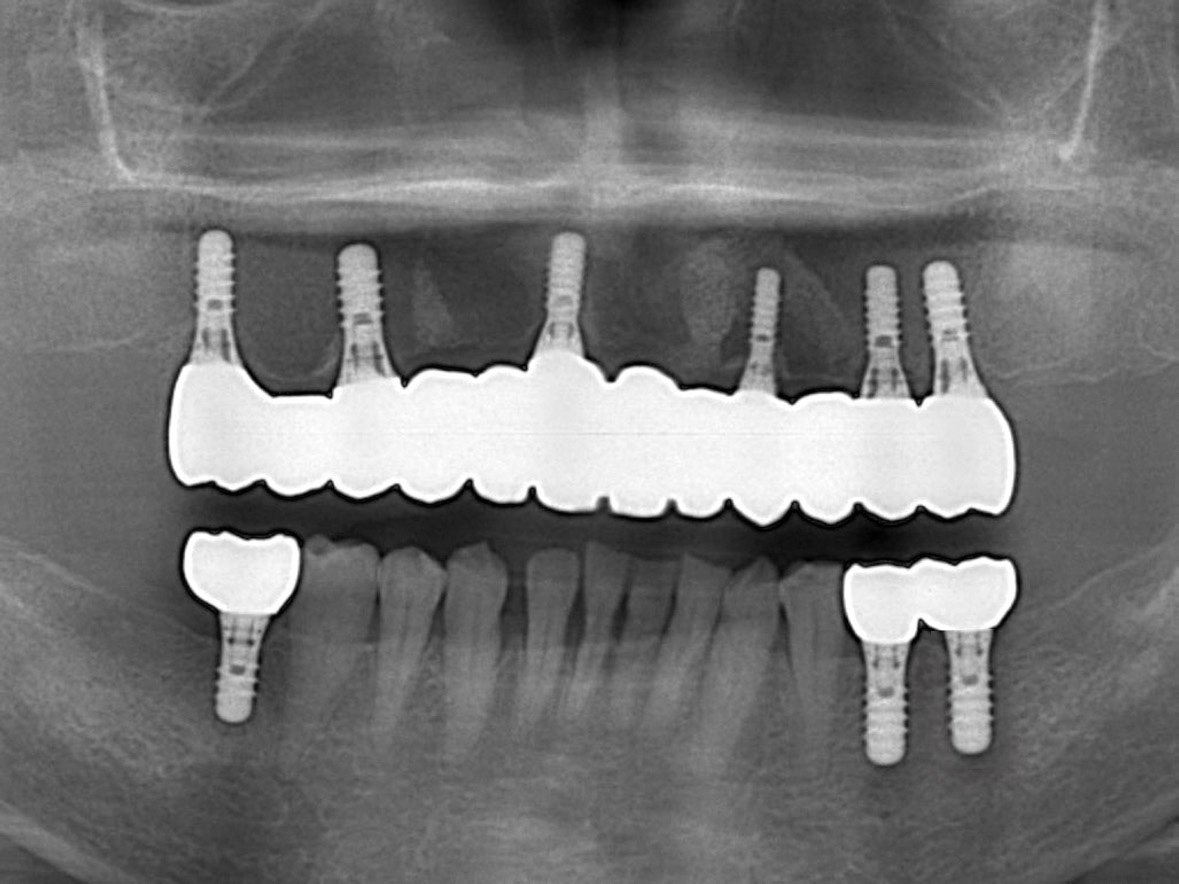

患者様の年齢 70代女性 主訴 入れ歯が痛い 噛みにくい 治療内容 上顎オールオン6

下顎臼歯部3本インプラント治療

抜歯即時インプラント埋入後3ヶ月の待機期間後、ジルコニアによる上部構造装着費用 456万円 治療期間・通院回数 6ヶ月/8回 デメリット・リスク 外科処置に伴う痛み・腫れ・出血・合併症の可能性があります。 -